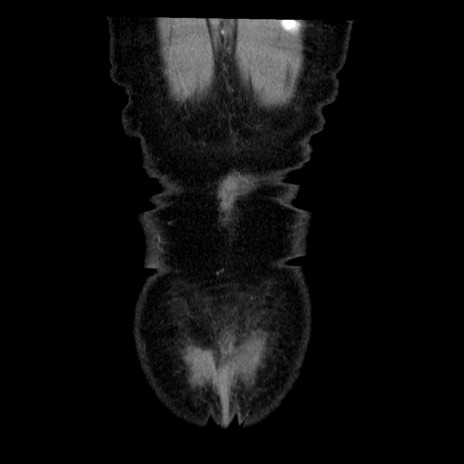

横断像

矢状断像